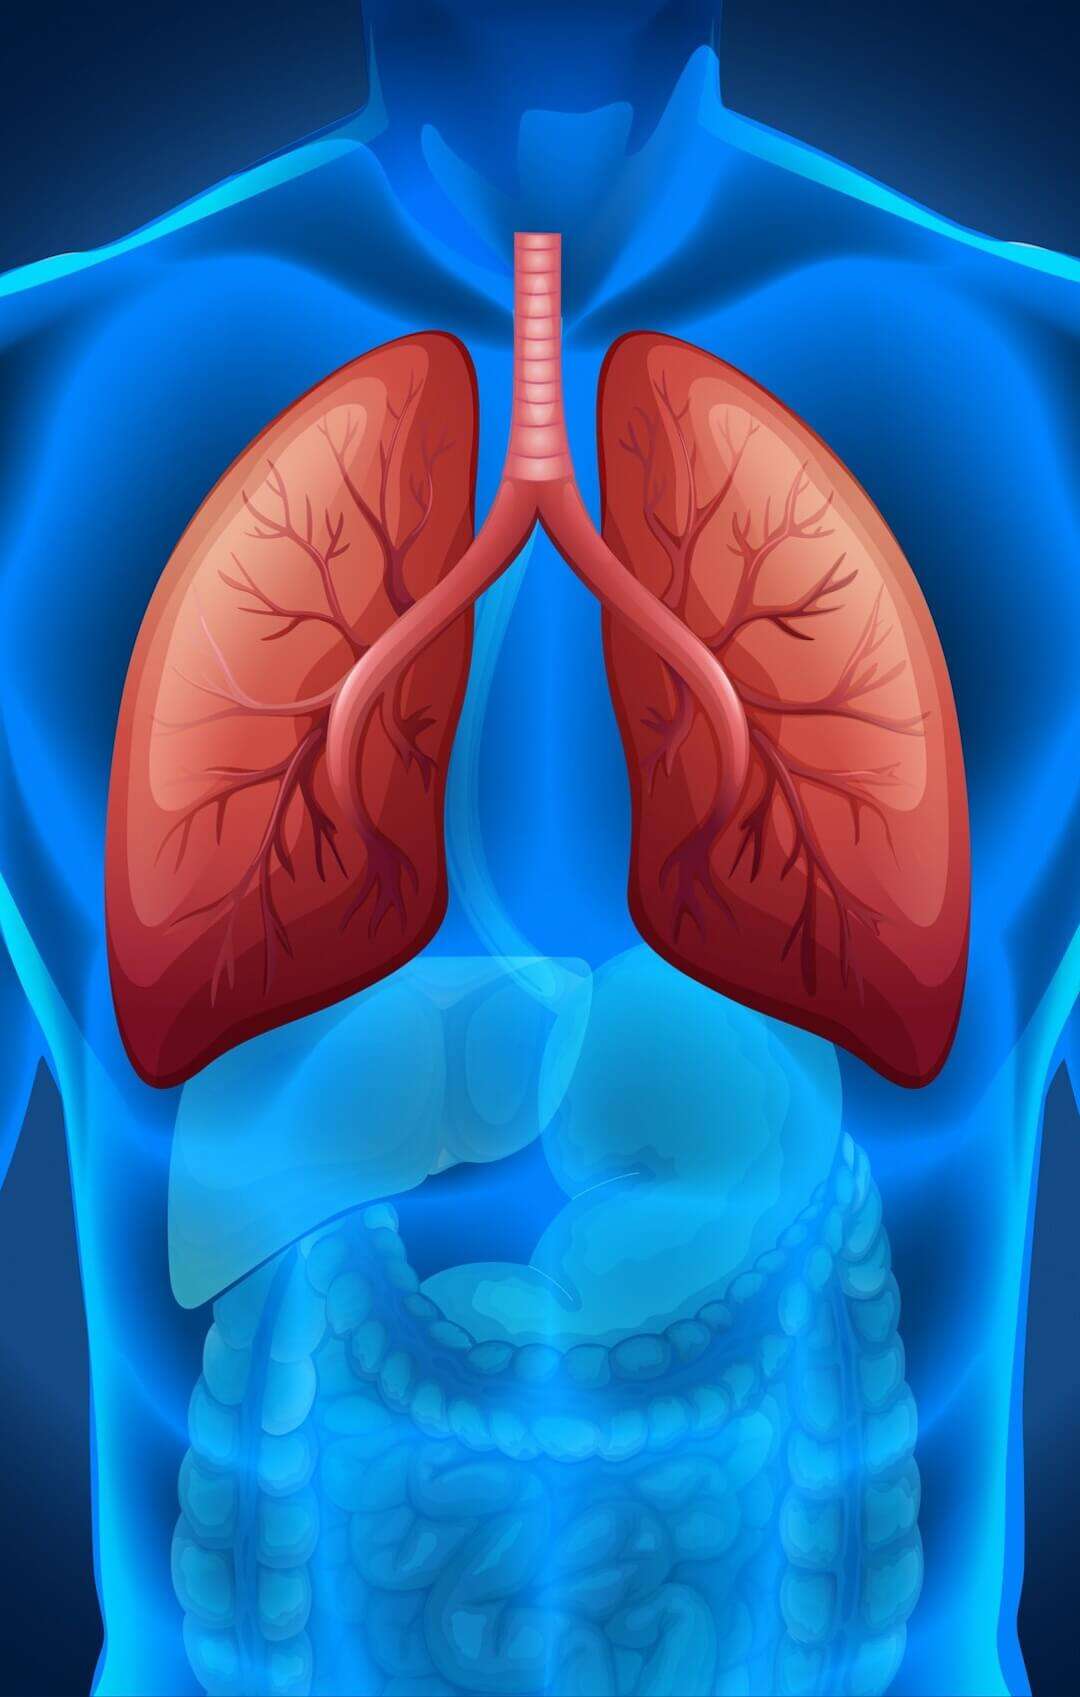

Hablar de cáncer de pulmón no debería ser un tema tabú ni un motivo de alarma injustificada. Al contrario, es una conversación necesaria para promover conciencia, información y prevención. Los pulmones cumplen una función esencial: permiten el intercambio de oxígeno que hace posible la vida. Sin embargo, también pueden verse afectados por enfermedades graves que, en muchos casos, comienzan de manera silenciosa.

El cáncer de pulmón se produce cuando se desarrollan células anormales que crecen de forma descontrolada en el tejido pulmonar. Con el tiempo, estas células pueden formar un tumor capaz de alterar la función respiratoria. En determinadas circunstancias, también pueden extenderse a otras partes del cuerpo, proceso conocido como metástasis. Existen distintos tipos de cáncer pulmonar, pero para la población general lo más relevante es identificar los factores de riesgo y reconocer señales de alerta.